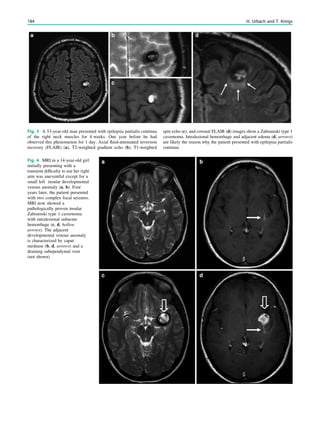

Academy of Neurology and the American Epilepsy Society.

Neurology 69(21):1996–2007. doi:10.1212/01.wnl.0000285084.

93652.43

Pohlmann-Eden B, Newton M (2008) First seizure: EEG and

neuroimaging following an epileptic seizure. Epilepsia 49(Suppl

1):19–25. doi:10.1111/j.1528-1167.2008.01445.x

Schreiner A, Pohlmann-Eden B (2003) Value of the early electro-

encephalogram after a first unprovoked seizure. Clin Electroence-

phalogr 34(3):140–144

Wiebe S, Tellez-Zenteno JF, Shapiro M (2008) An evidence-based

approach to the first seizure. Epilepsia 49(Suppl 1):50–57. doi:

10.1111/j.1528-1167.2008.01451.x